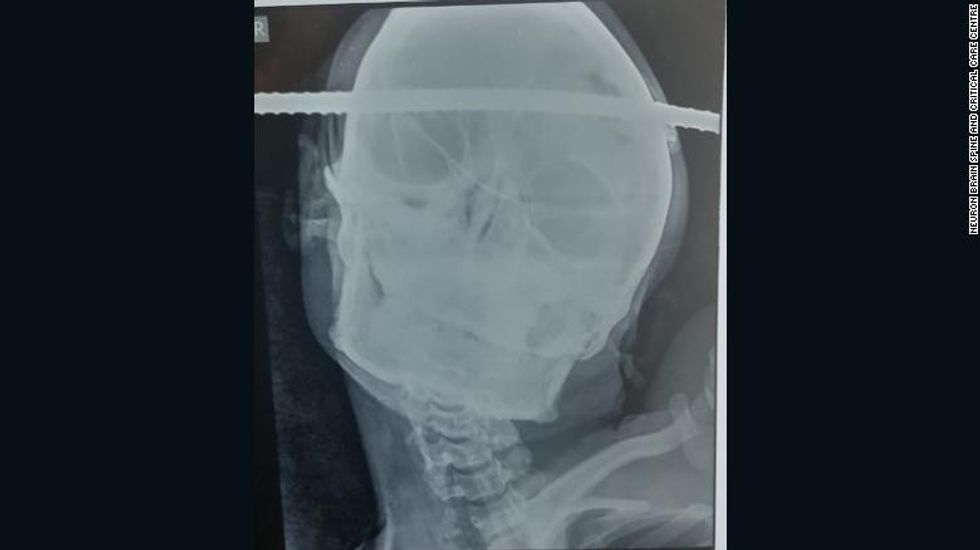

21-vjeçari po bënte riparime në një pus në distriktin Balaghat në shtetin Madhya Pradesh kur ai ra dhe shufra e hekurit i përshkoi kafkën dhe trurin.

Shufra kishte hyrë në pjesën e djathtë të kokës dhe kishte dalë në pjesën e majtë, duke shmangur për milimetra një enë gjaku të rëndësishme.

Duhej një grup prej 6 doktorësh që të hiqnin shufrën nga kafka e pacientit, i cili fitoi ndërgjegjjen disa orë pas operimit dhe nuk pësoi dëmtime në tru. Ai pritet të dalë nga spitali këtë javë. /oranews/